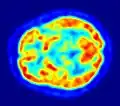

Utiliza-se glicose ligada a um elemento radioactivo (normalmente flúor radioactivo) e injecta-se no paciente. As regiões que estão metabolizando essa glicose em excesso, tais como tumores ou regiões do cérebro em intensa actividade aparecerão em vermelho na imagem criada pelo computador. [1][2] Um exemplo de um grande utilizador de glicose é o músculo cardíaco - miocárdio. Um computador produz uma imagem tridimensional da área, revelando quão activamente as diferentes regiões do miocárdio estão utilizando o nutriente marcado. [3]A tomografia por emissão de positrões produz imagens mais nítidas que os demais estudos de medicina nuclear. A PET é um método de obter imagens que informam acerca do estado funcional dos órgãos e não tanto do seu estado morfológico como as técnicas da radiologia. [4]A PET pode gerar imagens em 3D ou imagens de "fatia" semelhantes à tomografia computadorizada.[1]

Imagem PET de um cérebro humano